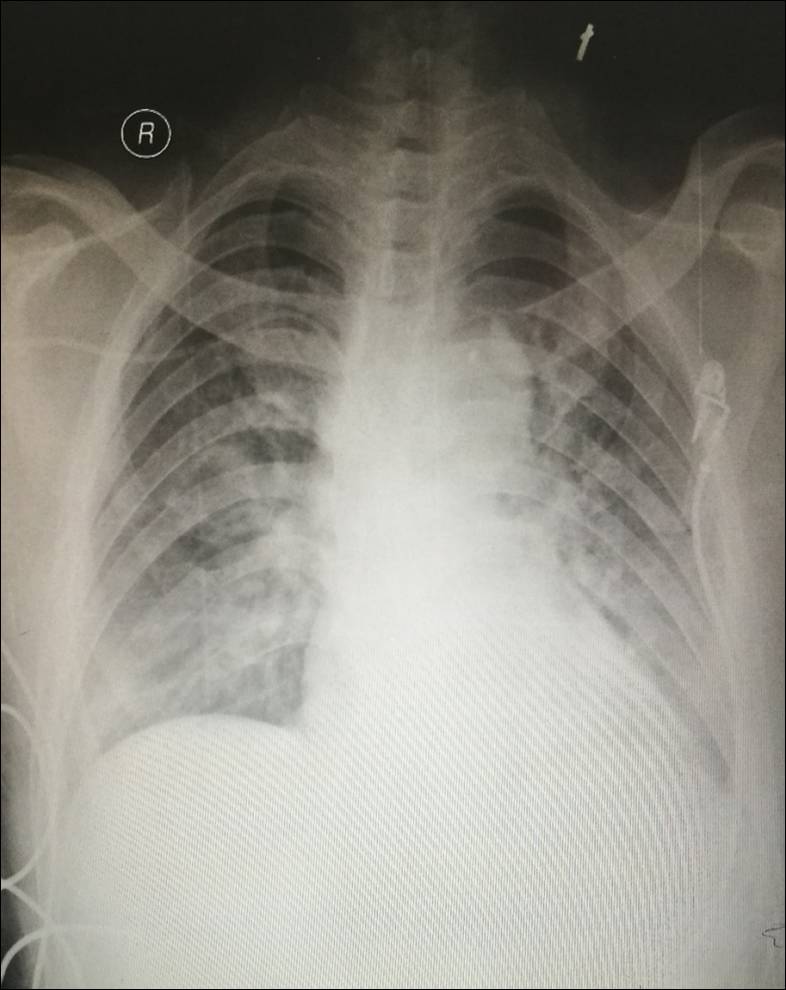

2016-11-29 -----成功撤除ECMO

ECMO运行4天,患者各项生命体征平稳,心脏彩超:EF值45-50%